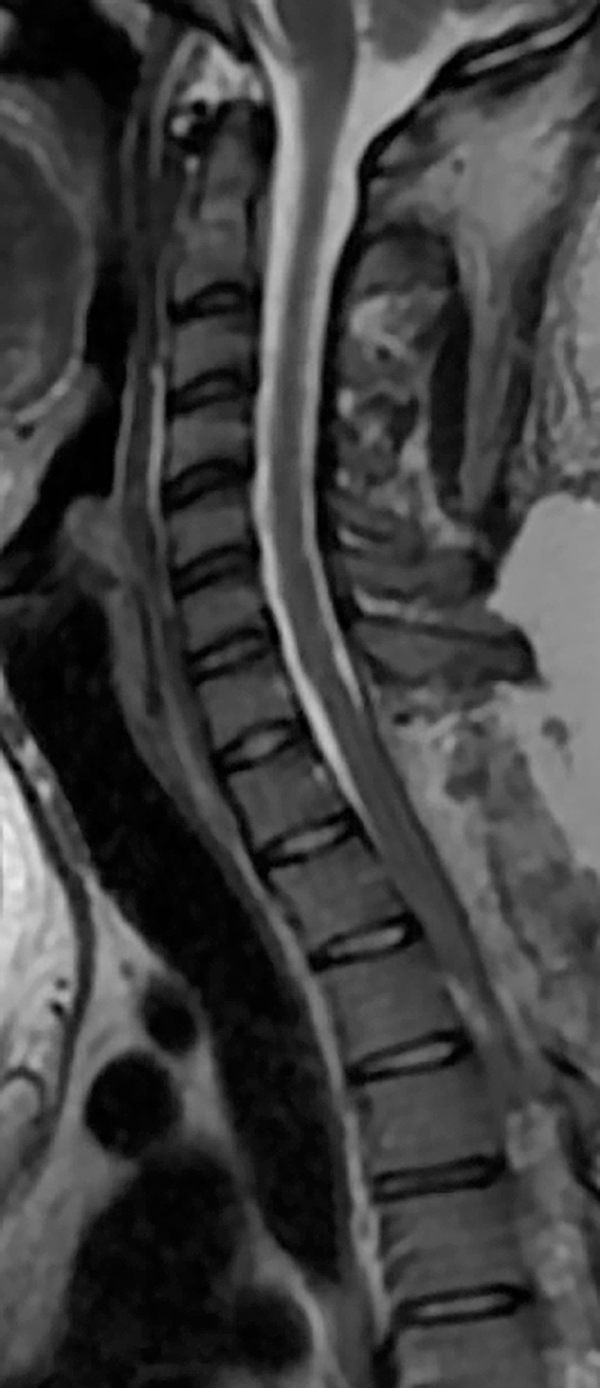

La paciente evolucionó favorablemente desde el postoperatorio inmediato hasta la actualidad (4 meses posteriores), con mejoría parcial de la paraparesia y parestesias, y recuperación de la deambulación (Figura 4).

Figura 4: RMN en secuencia T2 de control postoperatorio, en donde se observa ausencia de la lesión quística y recuperación de la configuración habitual de la médula espinal.